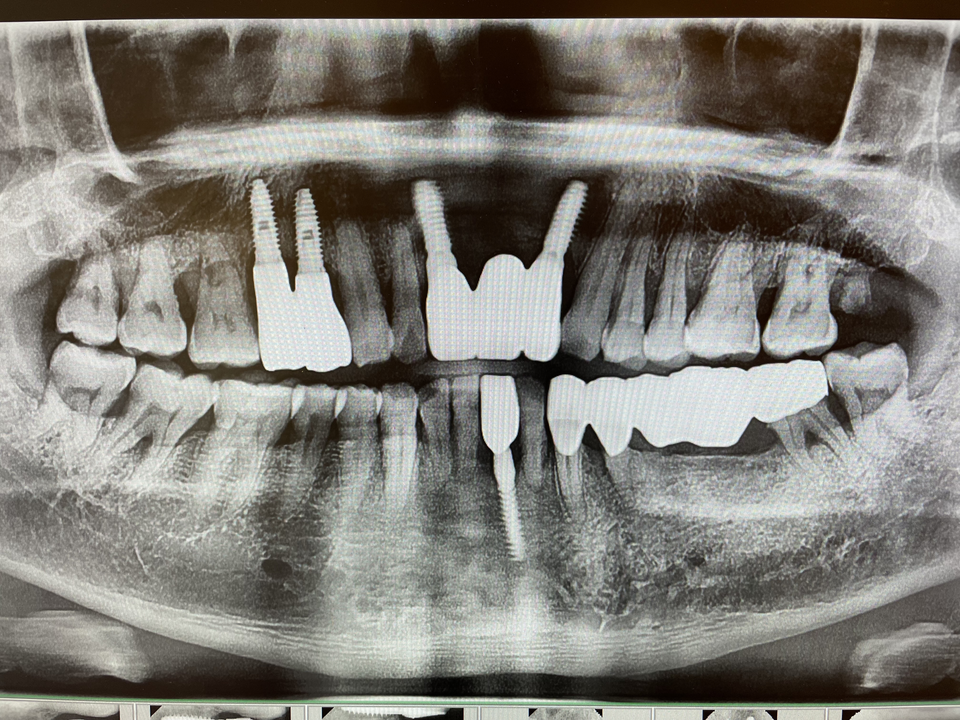

Bright implant 첫인상은 심플하고 깔끔하다. 수술키트도 손바닥만 하고 드릴링 3번이면 식립수술이 완료된다. 그 어떤 임플란트보다 간단하다. 너무 간단해 보여서 이걸로 될까 하는 생각이 들었지만 아주 알차게 잘 구성됐고, 드릴링도 매우 부드럽 고 시술시간은 매우 짧다.

기존의 덴티움 fixture는 매우 정교한 드릴링을 하지 않으면 식립 시 강한 마찰토크가 나올 경우 fixture 깊이를 딱 맞추기 어려워 수술시간이 길어지는 등 매우 섬세한 손이 요구됐다.

Bright implant는 fixture 코어는 작게, 측면 나사선(윙)을 넓게 만든 디자인이다. 드릴링단계가 단순하기 때문에 뚝딱 심을 수 있다.

최근 들어 치과의사들의 관심을 받는 fixture 디자인 트렌드가 바로 작은 코어와 넓은 윙이며 적은 드릴링과 높은 초기고정으로 술자에게 안도감을 주기에 한번 사용해 보면 또 찾게 된다.

물론 강한 골질을 만나 식립토크가 크게 걸릴 수 있고 fixture 윙의 변형이나 fixture 위치설정이 어려울 수 있다.

이 경우 식립 드릴링 시 골밀도를 꼭 체크해야 한다. 그렇다고 단단한 골질을 만나서 fixture가 변형이 생길까 미리 걱정할 필요가 없다.

Bright implant는 재질이 cold work grade 4로 제작되어 grade 5 수준의 강도를 가지고 있다. Bright implant는 높은 초기 고정력이 있어 즉시 및 조기 부하도 가능하다. 참고로 헤드가 작아서 토크렌치를 돌릴때 작은 헤드 부분이 덜 걸려 미끄러질 수가 있다. 꽉 누르고 토크렌치를 돌리는 것이 좋다.